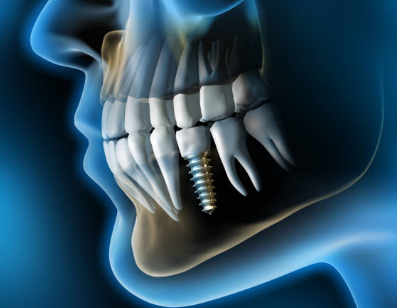

임플란트의 사전적 의미는 다음과 같습니다. 임플란트는 상실된 치아를 인공 치아 이식을 통하여 건강한 구강을 가지게 하는 의학 분야를 뜻합니다.

본래에는 인체의 조직이 상실되었을 때 이를 회복시켜 주는 대체 물질을 의미하지만, 치과에서는 인공 치아 이식의 의미를 지니기도 합니다. 이해를 쉽게 하기 위하여 다시금 말씀드리면, 인공적인 치아를 상실된 치아부위의 잇몸 뼈에 식립을 한 후, 그 위에 인공치아를 장착하여 수복하는 치료 방법을 말하는 것입니다.

2. 치아 발치 및 1차 시술

임플란트가 필요한 치아의 발치를 실시한 후, 그곳에 1차 시술을 진행합니다. 1차 시술은 턱뼈에 임플란트 인공치근을 식립하고 잇몸을 덮는 과정을 뜻하며, 이 과정에는 필수 기간이 필요하며 일정기간 동안 인공치근과 턱뼈가 잘 붙도록 기다려야 하는데, 일반적으로 아래턱은 약 2~3개월, 윗턱은 약 4~6개월 소요됩니다.

3. 2차 시술

인공치근이 잇몸뼈에 잘 자리 잡은 후, 덮어진 잇몸을 다시 열어 인공치근을 밖으로 노출시킵니다. 이때 진행하는 시술을 인공치근과 지대주를 연결하는 2차 시술이라 합니다. 지대주는 인공치근과 치아머리 크라운을 연결하는 기둥 역할을 하며, 2차 시술 후 잇몸이 완치되는데 약 1~2주 정도 걸립니다.